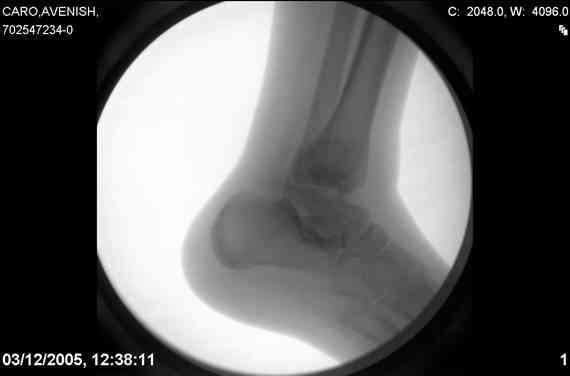

ya by popytalsya sobrat talus anatomichno,seichas pozdno operirovat iz za oteka,po etomy distrakziya apparatom budet optmalna.Posyalu vam podobyai moi sluchai.

14 years old girl

Fall from height ( 3rd floor)